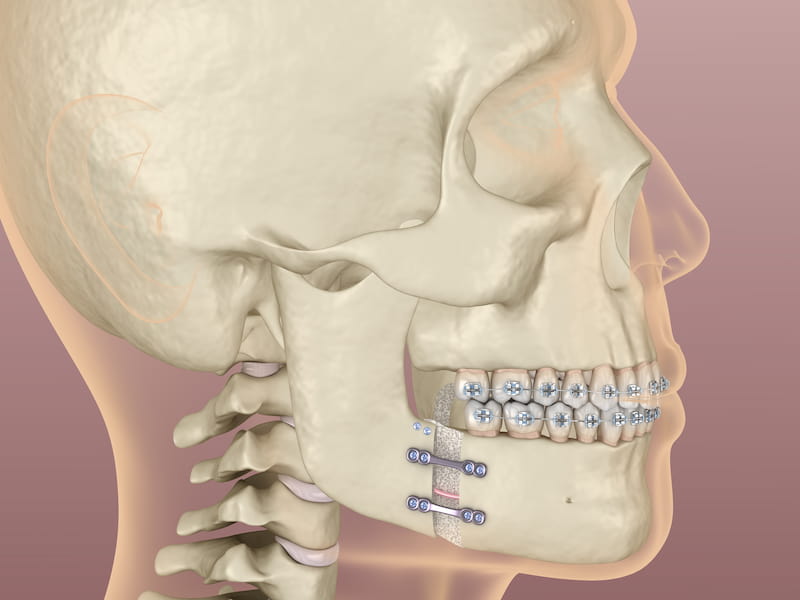

مشخصات ایمپلنت فک کامل

ایمپلنت فک کامل، راهی عالی برای جایگزین کردن دندانهای گمشده است و باعث تقویت قوس های فکی و بهبود خط بندی نیز میشود.